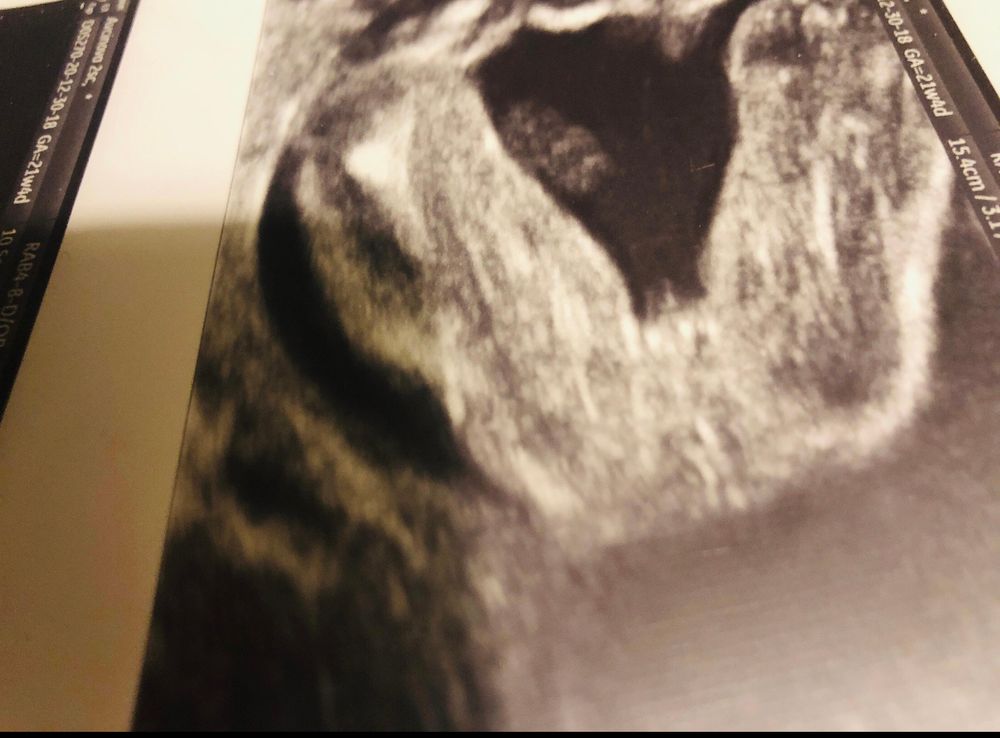

Пуповина или мужчина)?

Мальчик!

Мальчик конечно. Поздравляю!

Пацан конечно ☺️

Мужчина) у девочек иначе пирожок выглядит)

у моей по другому были девичьи признаки, предположу что М, только потому что у моей было не так.

Похоже на мальчика

Мужчина 😊